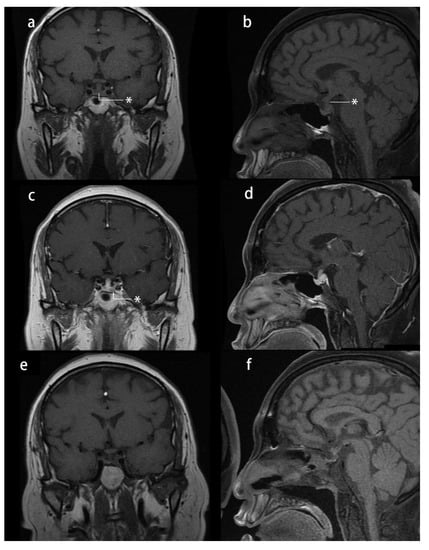

Her physical examination revealed moon face, central obesity, abdominal striae, and lower extremity edema. Her height was 164 cm, and her weight was 83 kg, with a body mass index (BMI) of 30.86 kg/m2. She had a history of hypertension, impaired glucose tolerance, and hyperlipidemia and had 5 months of menopause. Her blood pressure was approximately 130/80 mmHg when on a daily dose of 30 mg of nifedipine. Her midnight serum cortisol was 17.37 µg/dL, and her ACTH level was 55.7 pg/mL (reference range: 0–46 pg/mL), with 24 h urinary-free cortisol (24 h UFC) of 186.53 µg (reference range: 12.3–103.5 µg). An overnight 1 mg dexamethasone suppression test showed unsuppressed serum cortisol (3.09 µg/dL), whereas a high-dose dexamethasone suppression test showed suppressed serum cortisol (1.09 µg/dL). Dynamic pituitary MRI revealed a 9.7 × 4.0 mm lesion at the left side of the pituitary gland, with a thickened pituitary stalk (4.3 × 2.9 mm) and the loss of T1 signal hyperintensity in the posterior pituitary gland (Figure 1). She received a diagnosis of CD based on these data. Furthermore, central diabetes insipidus was diagnosed based on a water restriction test: Urine osmolarity was 105 mOsm/kgH2O, serum osmolarity was 323 mOsm/kgH2O, and serum sodium was 156 mmol/L at 8 h water restriction. Urine output dropped from 4370 mL/24 h to 1440 mL/24 h after treatment with 0.1 mg desmopressin. However, the cause of diabetes insipidus and thickened pituitary stalk remained unknown. In transsphenoidal surgery, a soft white mass at the left side of the pituitary was resected, and a white-gray tough lesion in the posterior pituitary was sampled for biopsy. At 17 months of follow-up, she had no Cushingoid symptoms or sellar mass recurrence, with a thinner pituitary stalk (2.9 × 2 mm). As only a partial remission of diabetes insipidus was achieved, and hypopituitarism had developed, she was discharged with a prescription of 0.05 mg desmopressin twice a day, 1.25 mg prednisone daily, and 100 µg levothyroxine every day.

Figure 1.

Presurgical and postsurgical pituitary MRI study of case 1: (a–d) presurgical MRI study: (a) T1-weighted image (T1-WI) coronal plane reveals a thickened pituitary stalk *; (b) T1-WI sagittal plane reveals a thickened pituitary stalk and loss of hyperintensity * of the T1 signal in the posterior pituitary gland; (c) T1-WI contrast-enhanced coronal plane reveals a hypointense nodule * in the left side of the pituitary gland; and (d) T1-WI contrast-enhanced sagittal plane reveals a thickened pituitary stalk; (e,f) one-year postsurgical MRI study: T1-WIs showing a thinner pituitary stalk and loss of hyperintensity of the T1 signal in the posterior pituitary gland.